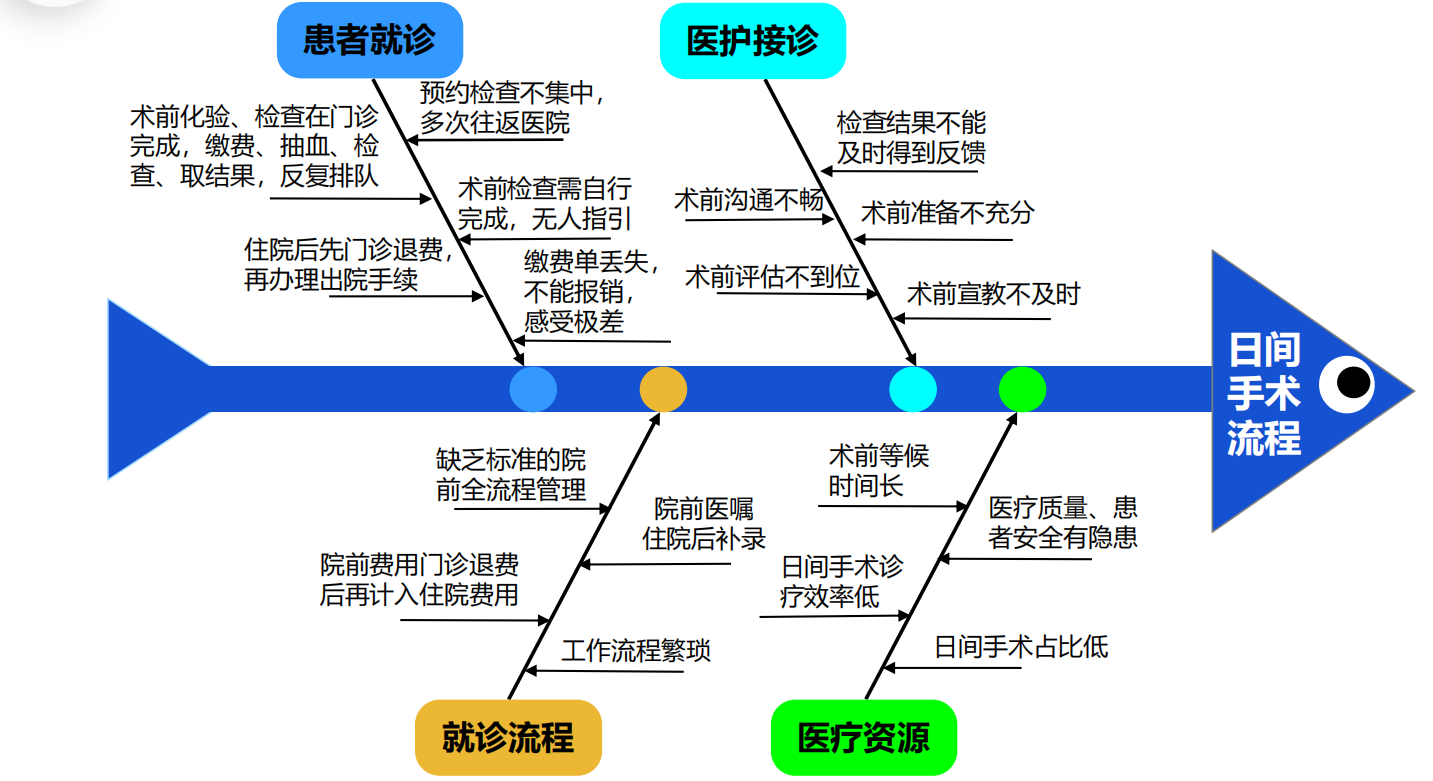

(一)优化冠心病介入诊治流程,缩短患者就医时间,保证医疗质量,建立冠心病介入治疗“日间病房”诊治新模式

广东省人民医院河源医院(河源市人民医院)积极响应国家号召,于2021年9月首次开展冠心病介入手术“日间病房”的创新模式。冠心病介入“日间病房”模式是一种高效、快捷、安全的手术模式,是以患者为中心、提高患者就医体验、改善患者就医感受、缩短患者就医时间为核心的创新型流程。具体流程为:①病情相对稳定的冠心病患者,在门诊就诊期间经过疾病和病情的初步评估,完善简单的肝肾功能等血液化验检查和心肺基本的影像辅助检查;②门诊医师通过冠心病患者的临床表现和检查结果进行全面评估,认为其适合接受冠脉造影及冠脉介入手术治疗;③预约固定某一天上午入院后,完善术前准备后送介入室或导管室进行手术检查及(或)介入治疗,手术过程顺利安返病房,经观察评估病情较为平稳,于当天下午或傍晚办理出院,回家休息。总结其为:入院-手术-出院于当天完成。

(二)整合心血管内科、介入导管室、医保部门和出入院部门等多个部门的人力与设备等资源,打造冠心病介入手术“日间病房”诊治单元

经过优化,这种冠心病介入手术“日间病房”模式变革了传统医疗观念,充分整合联动不同部门,形成高效率和高质量的诊疗单元,为患者带来诸多便利。在医生的指导下,患者通过门诊预约,完成相关检查后,患者可以当天入院接受手术,术后患者恢复迅速,无需陪护,缩短了住院时间,降低了医疗费用。这种模式不仅提高了医疗效率和质量,还减轻了家庭及国家的负担,广受患者的好评。